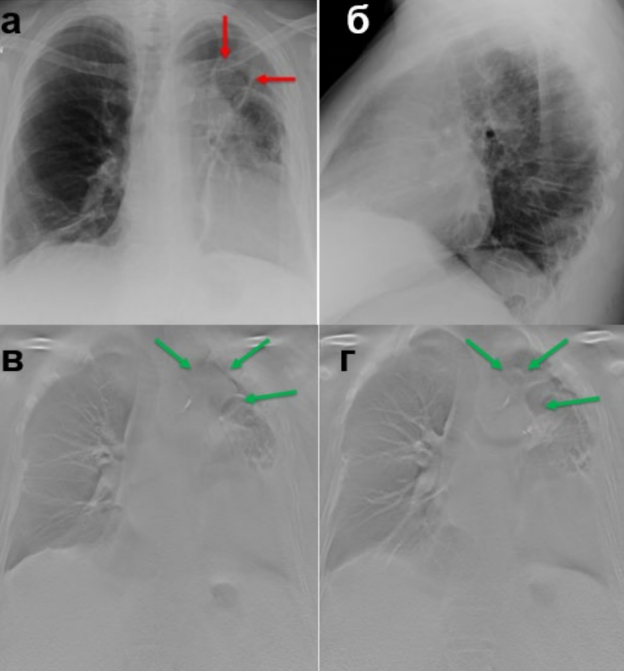

Послеоперационная гематома левого гемиторакса – описание в тексте (оригинальный рисунок): а – цифровая РГ ОГК в ПП; б – цифровая РГ ОГК в левой БП; в, г – ТС ОГК.

Состояние после реторакотомии слева, анатомической резекции 1-3 сегментов левого лёгкого. На обзорной рентгенограмме органов грудной полости – в проекции резецированных сегментов S1-3 определяется уплотнение с четкими неровными контурами – гематома? (красные стрелки). При ТС данные изменения выявляются более отчётливо (зелёные стрелки) – гематома.